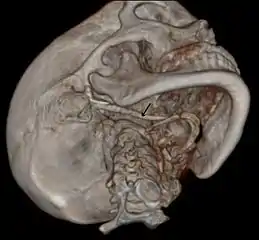

3D-reconstructed CT scan showing bilateral stylohyoid ligament ossification

3D reconstructed CT scan showing elongated styloid process (right side)

Imaging is important and is diagnostic. Visualizing the styloid process on a CT scan with 3D reconstruction is the suggested imaging technique.[11] The enlarged styloid may be visible on an orthopantogram or a lateral soft tissue X ray of the neck.